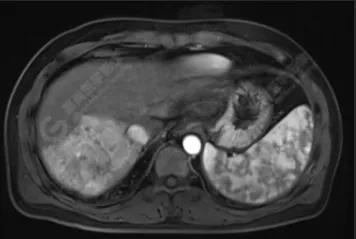

經(jīng)與放射科協(xié)調(diào),當(dāng)天即為該男士安排了上腹部磁共振平掃+增強(qiáng)檢查。

檢查結(jié)果如下:

肝硬化、原發(fā)性肝癌